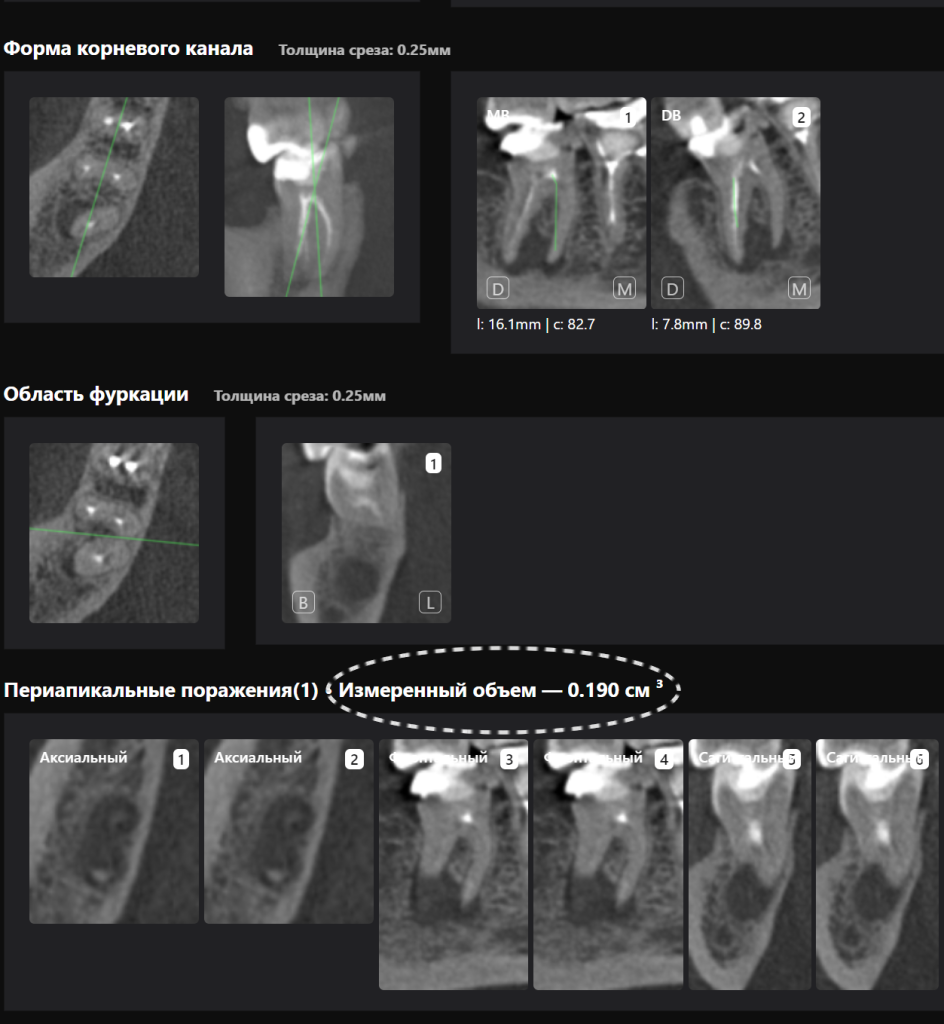

«Эндодонтический отчет» Diagnocat помогает зафиксировать изначальный объем периапикального очага и изучить анатомию и морфологию корневых каналов до начала лечения

А в «Эндодонтическом отчете» врач может объективно оценить положительную динамику, достигнутую на этапах лечения